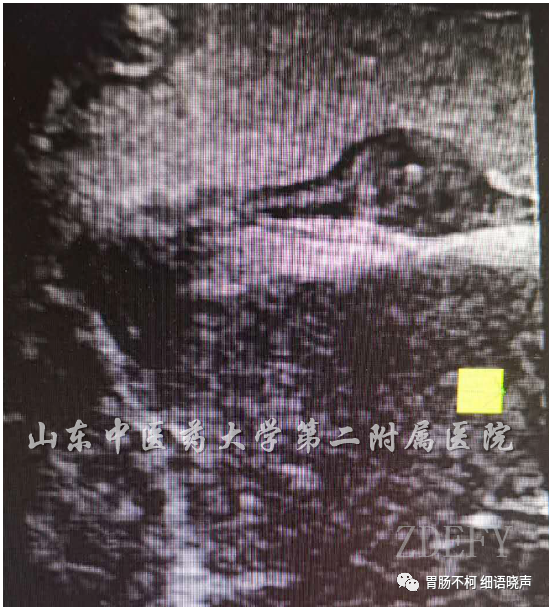

病例二:近贲门处胃体小弯侧黏膜下层来源扁盘状病灶,内呈网格状回声,可见“线样征”。